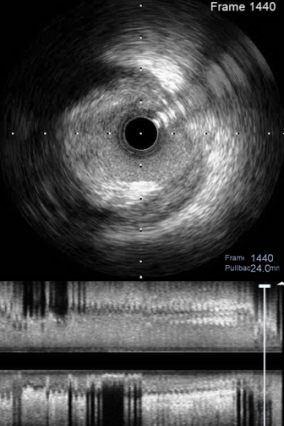

对RCA进行IVUS检查,可以看到RCA两处狭窄为纤维、钙化混合斑块,中段MLA为2.94mm²(图7);开口处MLA为4.53mm²(图8)。

图7

图8